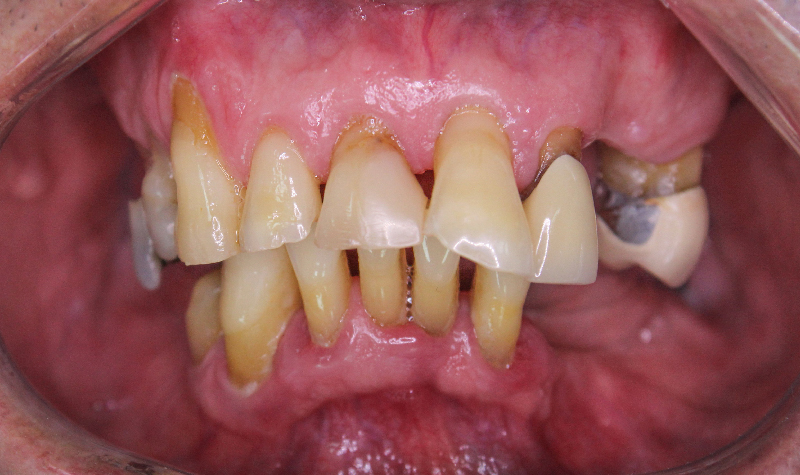

Rehabilitación Oral total con cerámicas sobre dientes e implantes.

Rehabilitación oral total de alta complejidad con cerámicas sobre dientes e implantes.